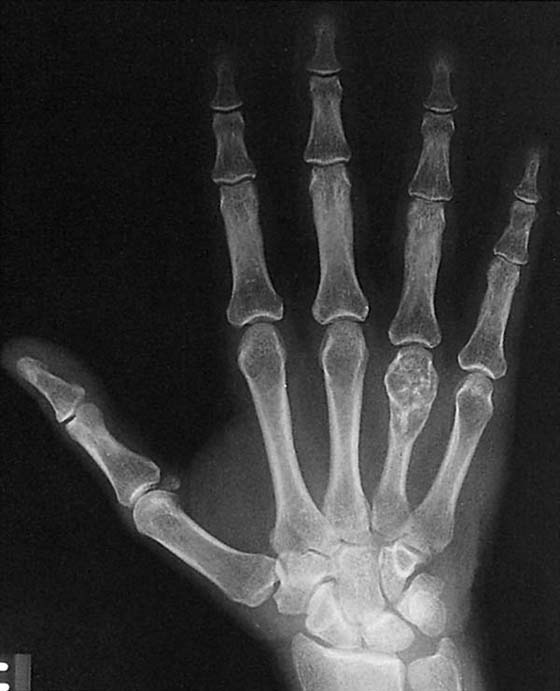

Routine studies of the hand consist of posteroanterior (PA), lateral, and oblique views, which are evaluated for bone density, bony lesions, fractures and dislocations, integrity of the articular surfaces and joint spaces, and irregularities of the soft tissue (Fig. 13-1).1

Figure 13-1 Routine views of the hand. A, Posteroanterior. B, Oblique. C, Lateral.

Bone density, which is evaluated grossly, may be normal, less than normal (osteopenia), or greater than normal (osteosclerosis). Osteopenia is most often encountered in the elderly and is known as senile osteoporosis when associated with advanced age. Osteosclerosis occurs in conditions such as avascular necrosis (AVN) (Fig. 13-2), fracture healing, and metabolic bone disease.2 Plain films may reveal discrete or diffuse bone lesions, including primary or metastatic bone tumors, infection, and metabolic bone disease (Fig. 13-3). The cortical integrity is carefully inspected for evidence of acute fracture (Fig. 13-4) and the joint alignment evaluated for subluxation or dislocation.3 Abnormalities of the articular surface and cartilage joint space also are documented. Narrowing of the cartilage space may indicate arthritis, resulting from degeneration, inflammation, infection, or trauma (Figs. 13-5 and 13-6).4 Finally, the soft tissue shadows are evaluated for irregularities. Any evidence of calcification (Fig. 13-7), foreign bodies (Fig. 13-8, online),5 or soft tissue masses must be correlated with the clinical findings.